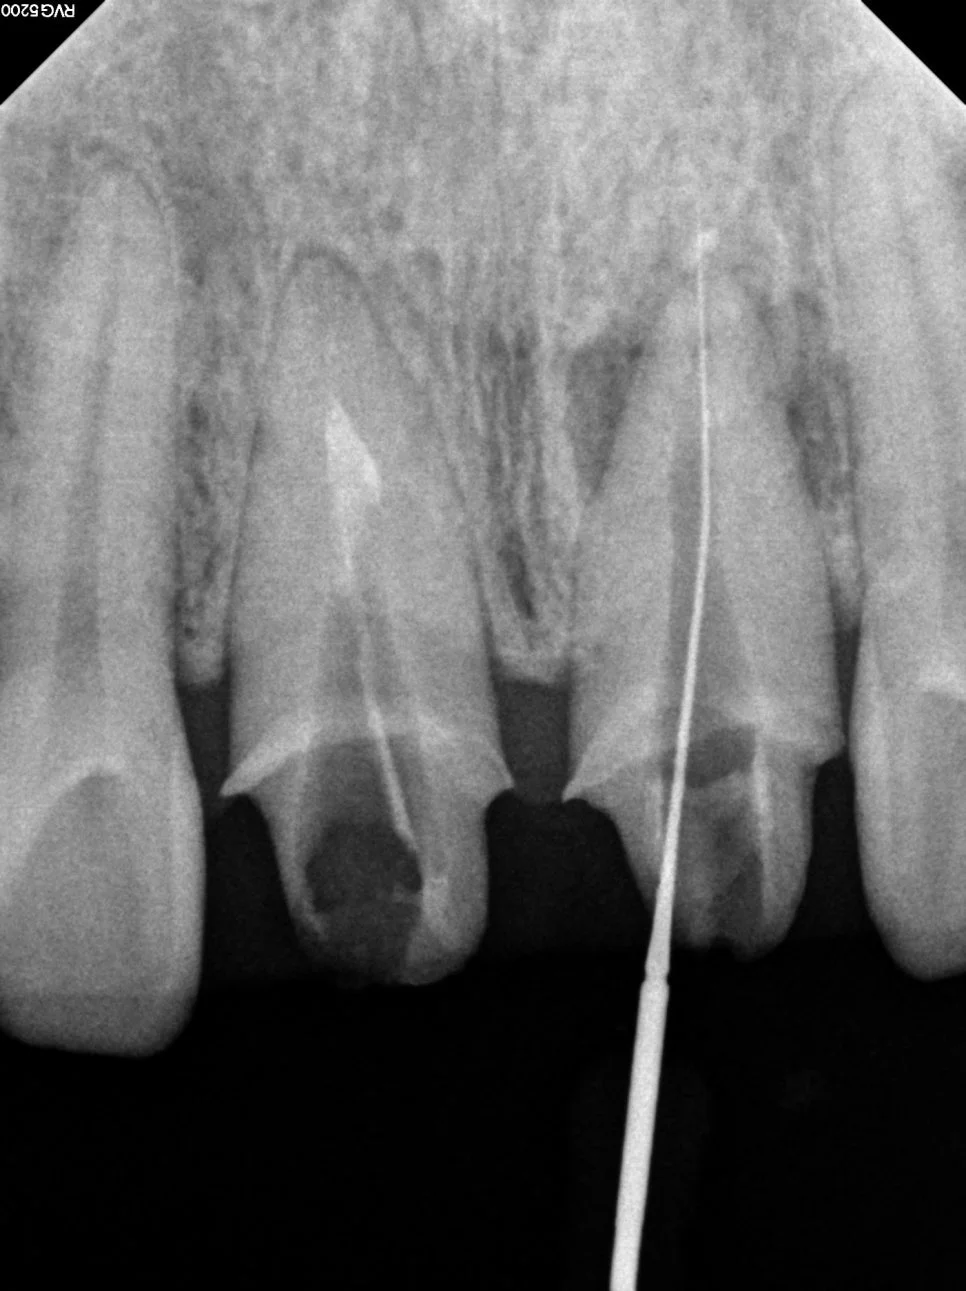

치근단 사진 — 뿌리 끝 염증 소견 관찰

치근단 사진에서 뿌리 끝 염증 소견이 관찰되어 크라운 제거 후 내부 상태 확인과 재신경치료가 필요하다는 결론에 도달했습니다.

재신경치료 — 신경관 확대 및 소독 과정 엑스레이

각 신경관이 뿌리 끝까지 제대로 이어져 있는지 경로를 먼저 확보하고, 안쪽에 남아있는 염증·세균을 없애기 위해 충분히 넓히고 소독해 줍니다.

재신경치료 완료 — 신경관 빈틈없이 충전 확인

마지막으로 신경관 전체를 빈틈 없이 충전해 줍니다.

치료가 끝난 후에는 X-ray를 통해 모든 신경관이 뿌리 끝까지 깔끔하게 차 있는지 확인하면 성공적인 재신경치료가 이루어진 것입니다^^